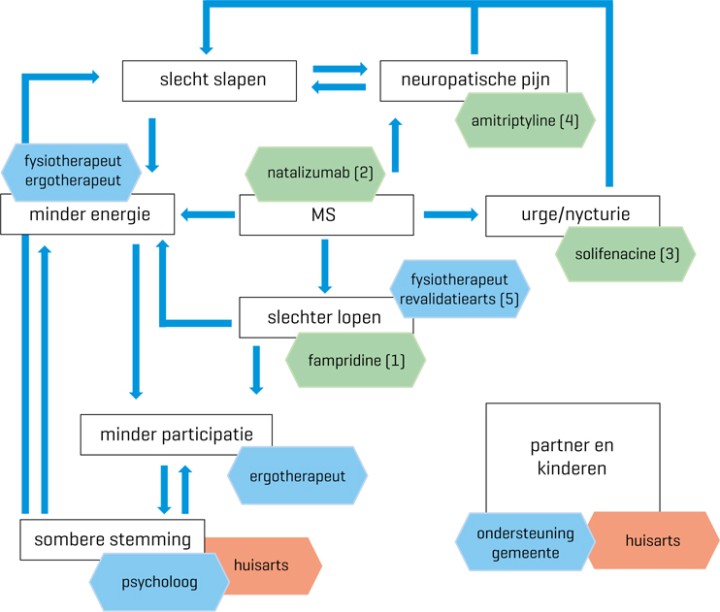

De neuroloog, fysiotherapeut, ergotherapeut en psycholoog stellen in samenspraak met Piet een behandelplan op [figuur 3]. Om het lopen te optimaliseren start Piet met fampridine (een kaliumkanaalblokker) en krijgt hij fysiotherapie na een loopganganalyse. Daarnaast probeert men de nachtrust te verbeteren en zijn er enkele gesprekken met de psycholoog om te achterhalen of er sprake is van een bijkomende depressie. Piet krijgt amitriptyline vanwege de neuropathische pijn die het inslapen belemmert, en solifenacine om de nycturie en de urgeklachten overdag te bestrijden. Al snel gaat het slapen wat beter, Piet moet nog hooguit eenmaal ’s nachts eruit om te plassen. Door de verbeterde nachtrust gaat het lopen ook iets beter. Met een paar aanpassingen wordt klussen in de schuur weer mogelijk gemaakt. Door deze merkbare verbeteringen van zijn kwaliteit van leven worden de somberheid en uitzichtloosheid minder. Ondertussen heeft de MS-verpleegkundige via de gemeente hulp en ondersteuning voor partner en kinderen geregeld, want ook zij moeten hun weg met de ziekte van Piet zien te vinden.

Figuur 3 | MS-problematiek en bijpassende interventies in de casus over Piet